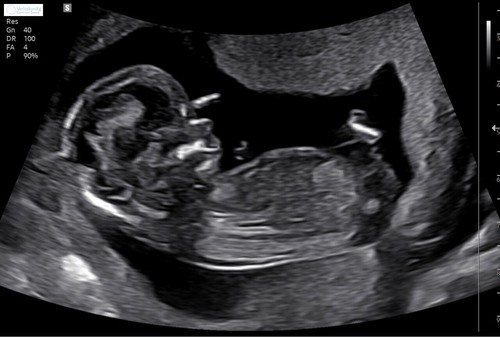

Deze

Dit zijn de foto's die ik heb, ik ben benieuwd heb er zelf totaal geen verstand van 馃グ

Door de andere foto neig ik meer naar een meisje 馃┓ maar kan het helaas niet goed zien